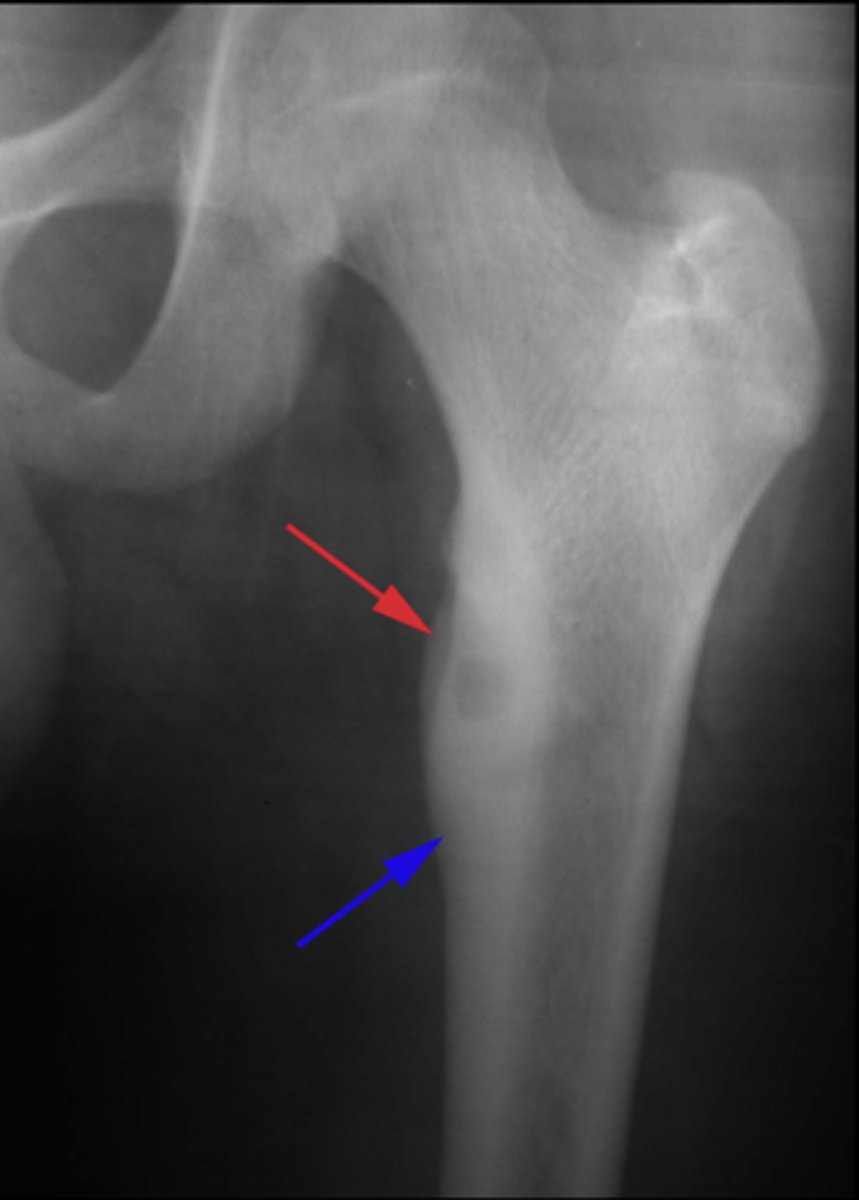

Geographic bone blister

ID radiographic feature of non-ossifying fibroma indicated by top arrow

Septations

ID radiographic feature of non-ossifying fibroma indicated by bottom arrow

Pathologic fracture

Non-ossifying fibroma with _____